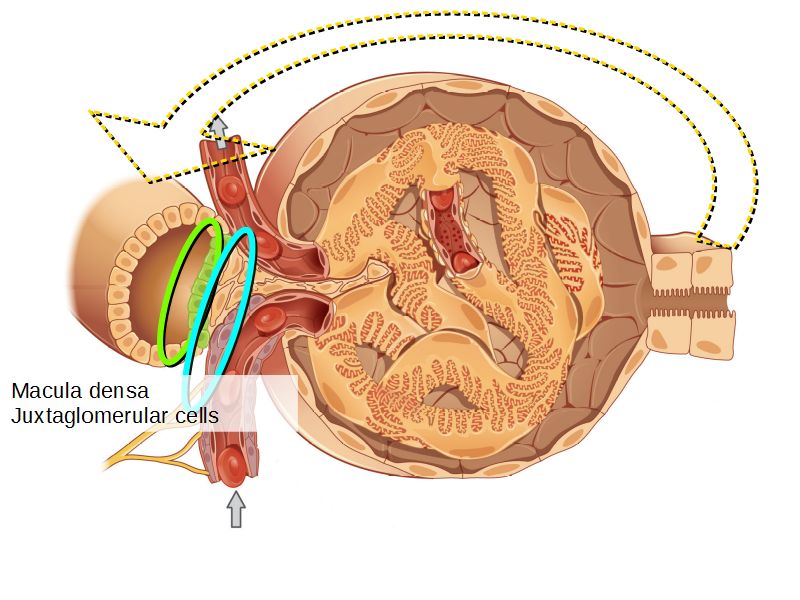

Juxtaglomerular complex

Area where distal convoluted tubule return to glomerulus and pass through the notch between the afferent and efferent arterioles. Modification of the wall of the tubule and afferent arteriole and presence of specialised cells in the connective tissue.Modifications

- Distal convoluted tubule

- Macula densa

- Narrow epithelial cells

- Nuclei densely packed

- CT cells

- Laci cells

- Similar to mesangial cells

- Afferent arteriole

- Modified smooth muscle cells

- Juxtaglomerular cells

- Secretory function